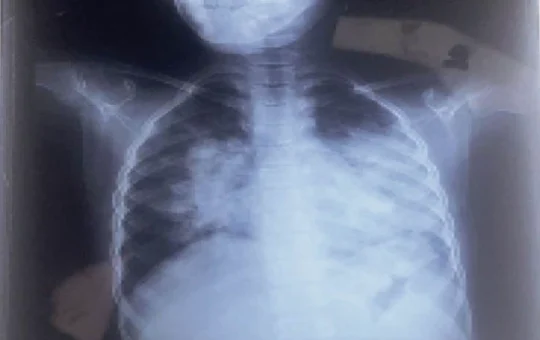

उत्तराखंड : ढाई साल की मासूम बच्ची इन्फ्लुएंजा-ए मिली पॉजिटिव, दून अस्पताल में किया गया आइसोलेट

उत्तराखंड : राजधानी देहरादून के दून अस्पताल में एक ढाई साल की बच्ची इन्फ्लुएंजा-ए के साथ ही एच-1 एन-1 पॉजिटिव...

बच्चों में बुखार सात से आठ दिन में भी पूरी तरह सही नहीं हो रहा है और उनके लंग्स भी...